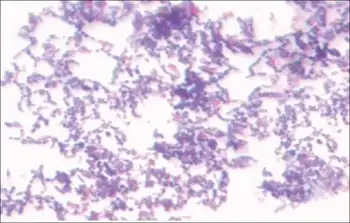

| Stain of S. mutans in thioglycollate broth culture. | |